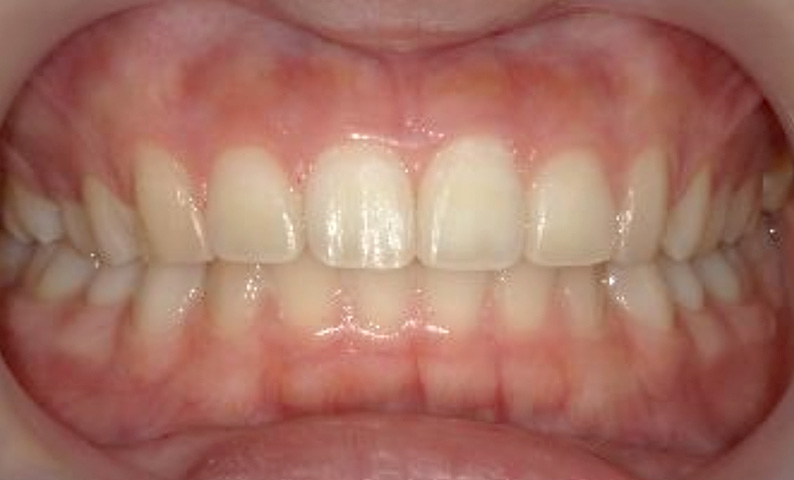

症例_002 上下顎の部分矯正

治療期間:7ヶ月金額:54万円+税女性前歯のガタガタ出っ歯八重歯

| Before | After |